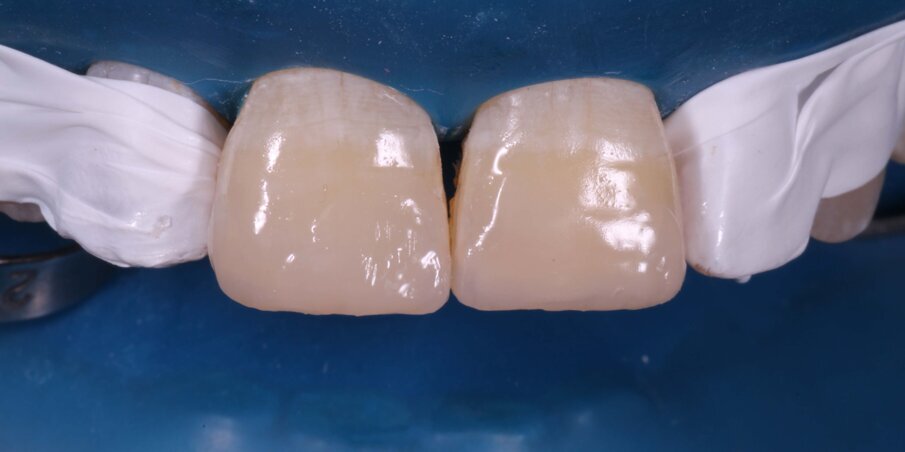

Enamel Shade A3 of a nanocomposite (FiltekZ350XT,3M) was adapted on the previously scored putty index, placed in position and light-cured for 20 seconds. This gave us the palatal shell on which we layered the Dentin and Body Shades (A3) sequentially (Fig 10 -12). Proximal walls were created with enamel shade composite and thin mylar strips with a palatal pull-through technique. A thin final layer of enamel shade was applied and photocured (Fig 13-14).

Fig 10: Building proximal walls in enamel shade composite after creating the palatal enamel shell

Fig 11: First layer of Dentin Shade Composite

Fig 12: Second layer of Body Shade composite

Fig 13: Final layer of Enamel Shade composite covering the entire bevel

Fig 14: Photocuring with glycerin gel barrier